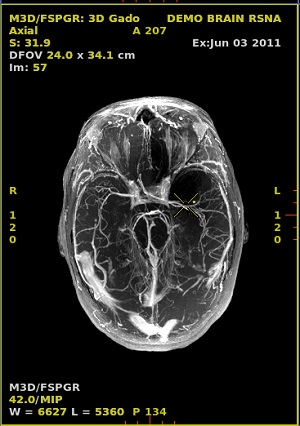

- From a 3D data set, create an MPR or Reformat image.

- Select the 2D view to change the slice thickness. Middle-click and drag to adjust the thickness in real time or left-click to decrease and right-click to increase the slice thickness. Alternatively, click the slider or type a desired value on the view.

- The small horizontal bars on either side of the single bar are used to adjust the MPR slice thickness.

Figure 4. 2D image